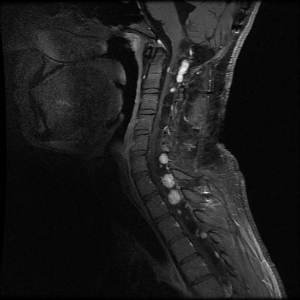

Figure 3. Hemangioblastomas are the most common disease manifestation in patients with von Hippel-Lindau disease. Multiple spinal cord hemangioblastomas are shown.